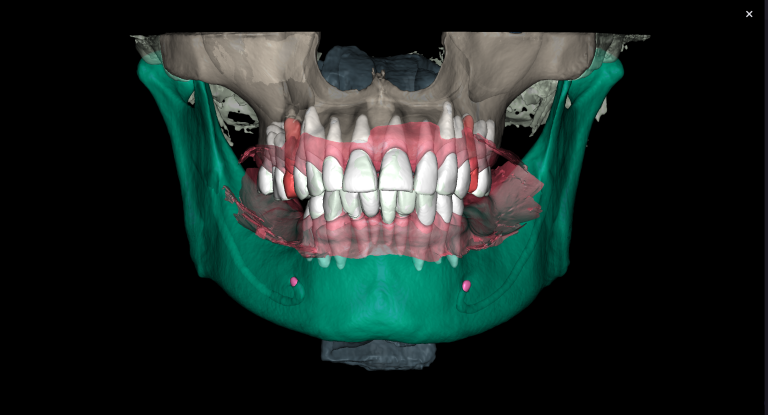

The slide illustrates the sequence of stages involved in prosthetic rehabilitation, obtaining digital impressions and uploading them to the Diagnocat STL module, to creating temporary crowns and forming the desired emergence profiles for implants

The slide demonstrates the continuation of prosthetic treatment on the lower jaw